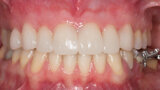

Fig. 3: Initial clinical situation.